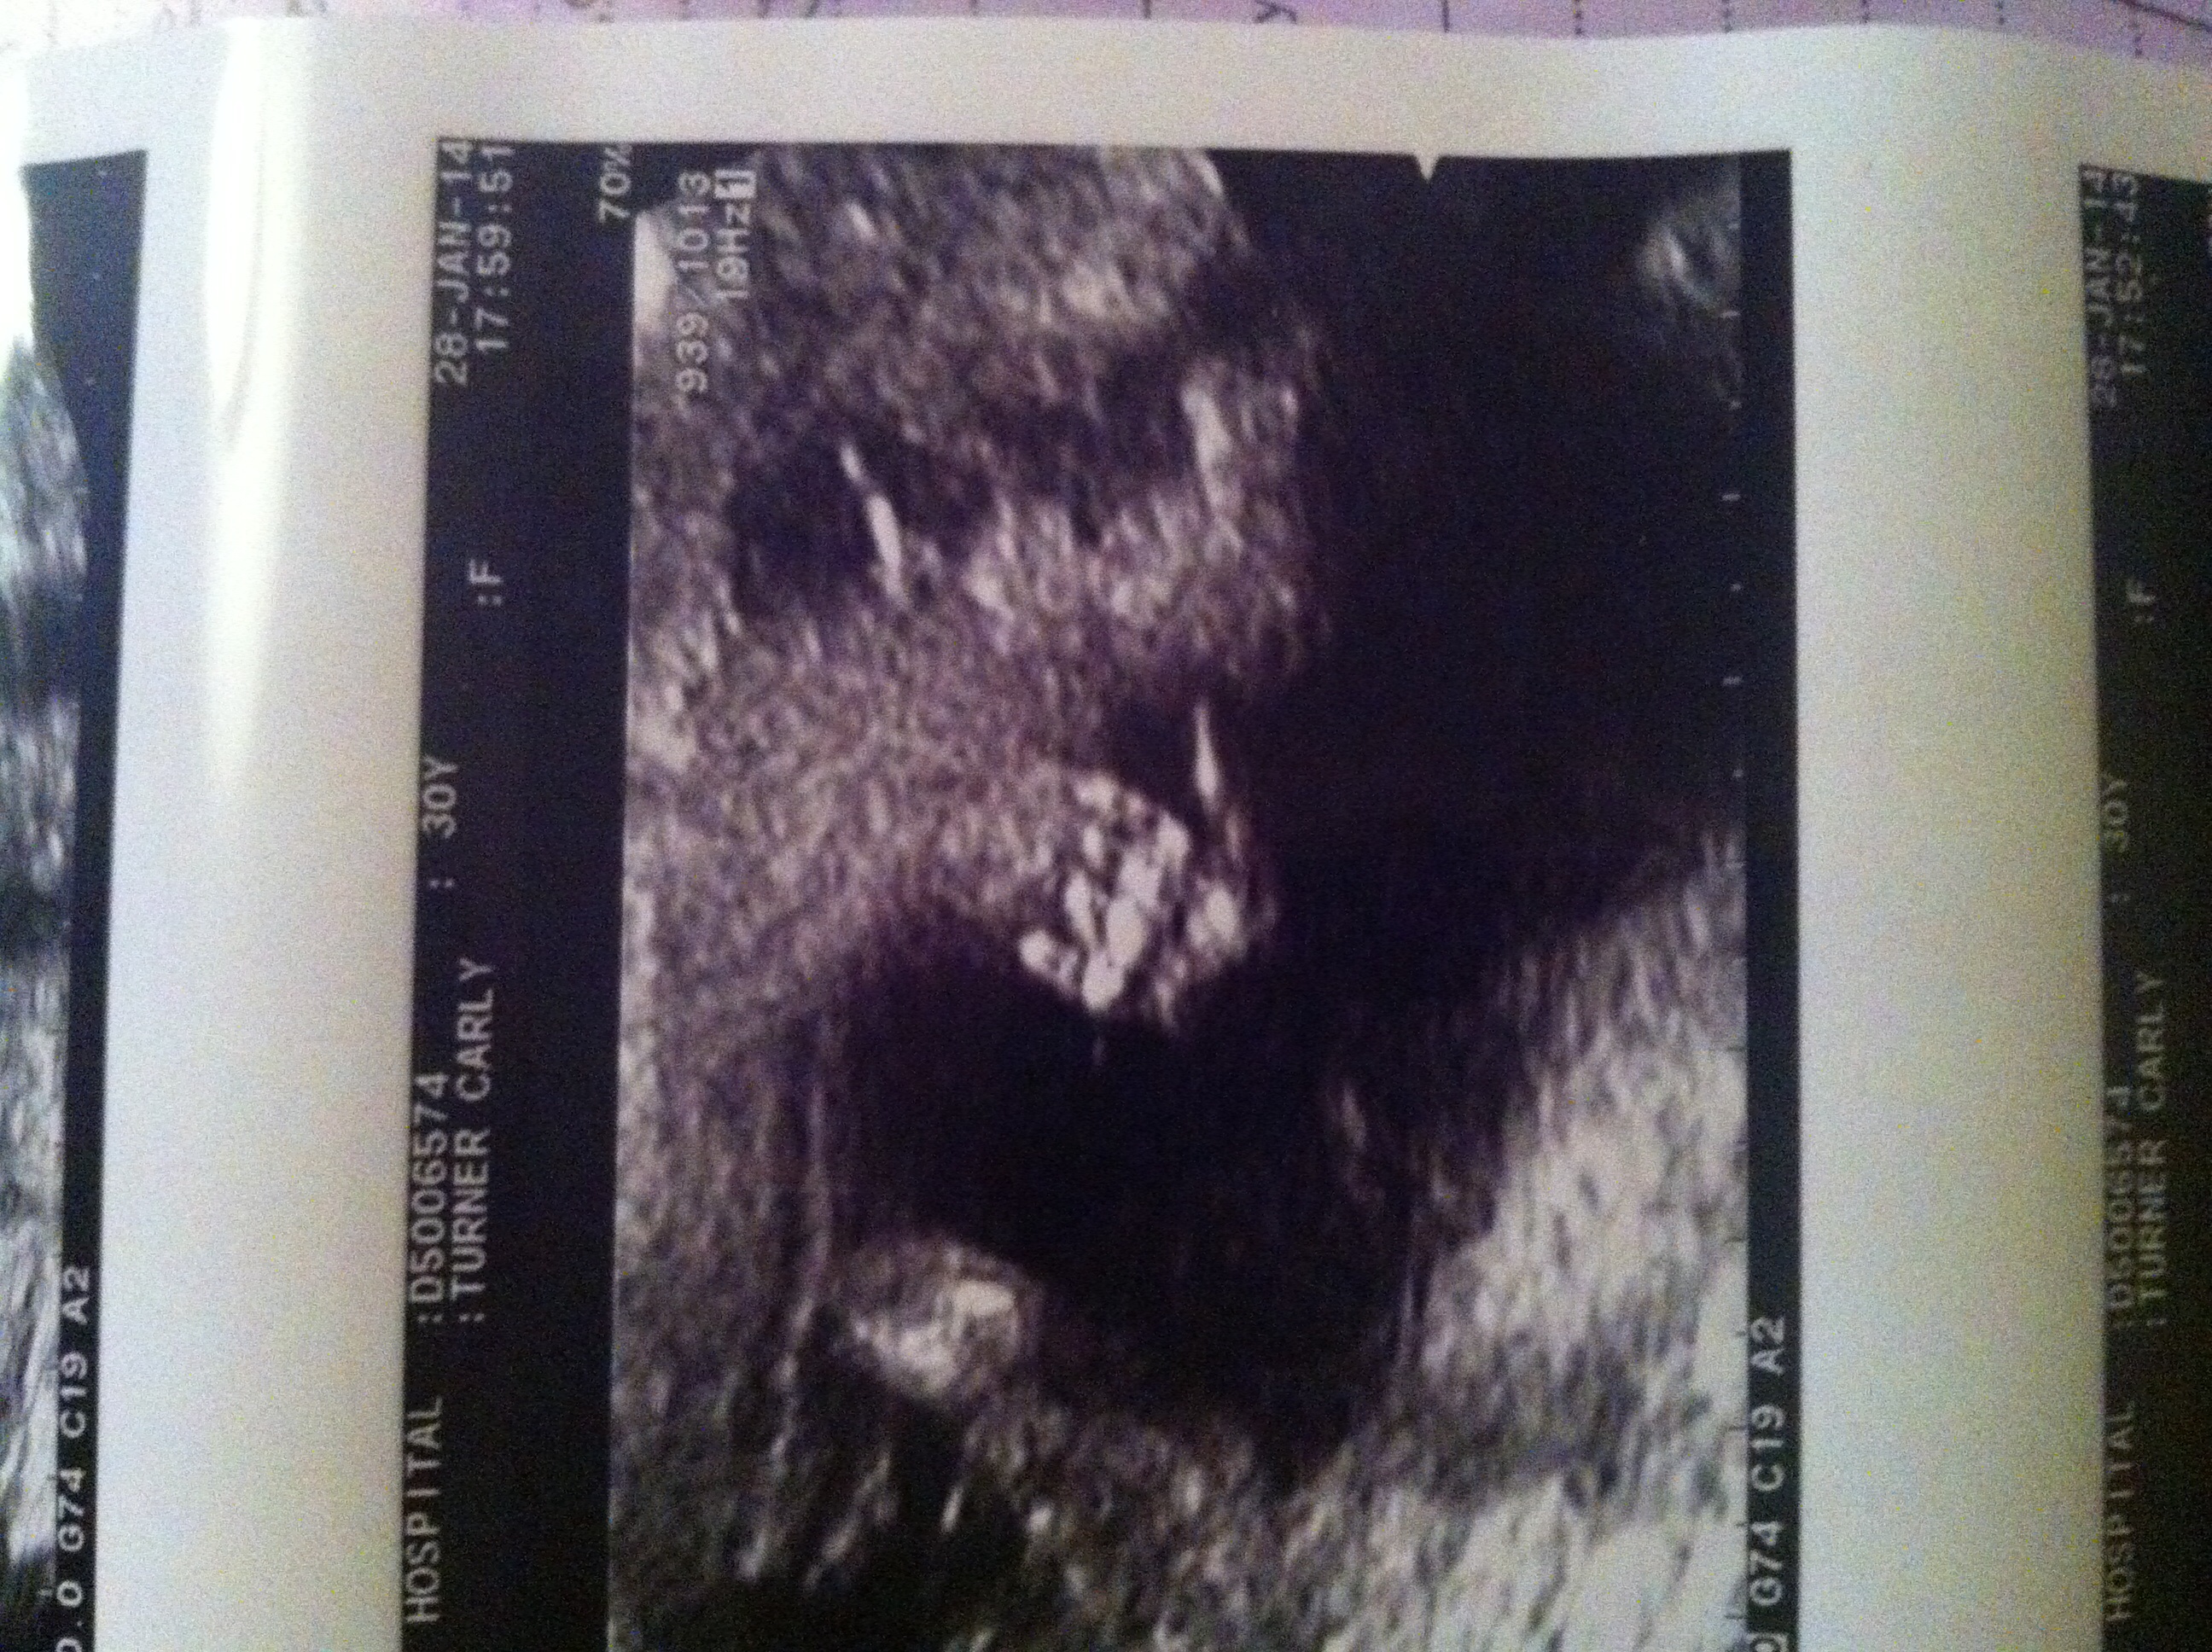

Me and baby are fine. My placenta is at the front so that's why they couldn't hear the heartbeat. They have also put me forward 6 days (making me 17 weeks today)! And the lady that did my scan said she thinks we are having a boy!!!

Also want to say a massive thank you for all your kind and supportive messages they meant so much and gave a lot of comfort. As I had to make the hour bus journey myself and go to the hospital on my own as my partner had to get my other two children from school. But once again massive THANK YOU ladies and I'm sorry you didn't see the update I put on the other post last night once I got home!! Here is a pic we got of our babies hand at the ultra sound scan yesterday. Was prob bloody waving at us wondering what all the fuss was about lol